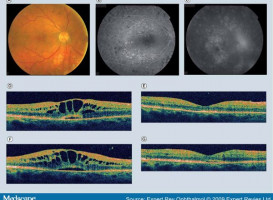

Fotografie této firmy